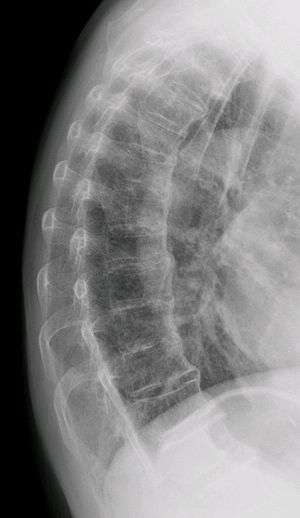

| Diffuse idiopathic skeletal hyperostosis. Woman of 80 years old, also with Th11 fracture. | |

Diffuse idiopathic skeletal hyperostosis (DISH) is a non-inflammatory spondyloarthropathy of the spine. It is characterized by spiny ankylosis and enthesopathy (ossification of the ligaments and entheses). It most commonly affects the thoracic and thoraco-lumbar spine, but involvement is variable and can include the entire spine.[1] The disc spaces, facet and sacroiliac joints remain unaffected. Diagnosis requires confluent ossification of at least four contiguous vertebral bodies.[1] Classically, advanced disease may have "melted candle wax" appearance along the spine on radiographic studies.[2]